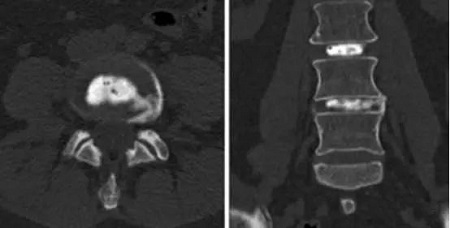

紐約spicial surgery 醫(yī)院的Gregory Lutz醫(yī)生報道了使用椎間盤內(nèi)PRP注射治療椎間盤退變的案例。患者是一位54歲的女性,嚴(yán)重的慢性腰痛,L4放射痛,L4-5椎間盤偏左側(cè)突出,接受過物理治療、非甾體類抗炎藥和介入治療,效果都不佳,2年后她接受了L3-4和L4-5椎間盤造影,發(fā)現(xiàn)L3-4正常,而L4-5誘發(fā)疼痛并發(fā)現(xiàn)纖維環(huán)裂隙?;颊呓邮芰薒4-5椎間盤內(nèi)注射PRP1.5ml治療,4周后疼痛幾乎完全緩解。18個月的隨訪疼痛和功能恢復(fù)非常滿意。

CT軸位和前后位顯示L4-5間盤造影和血小板注射。